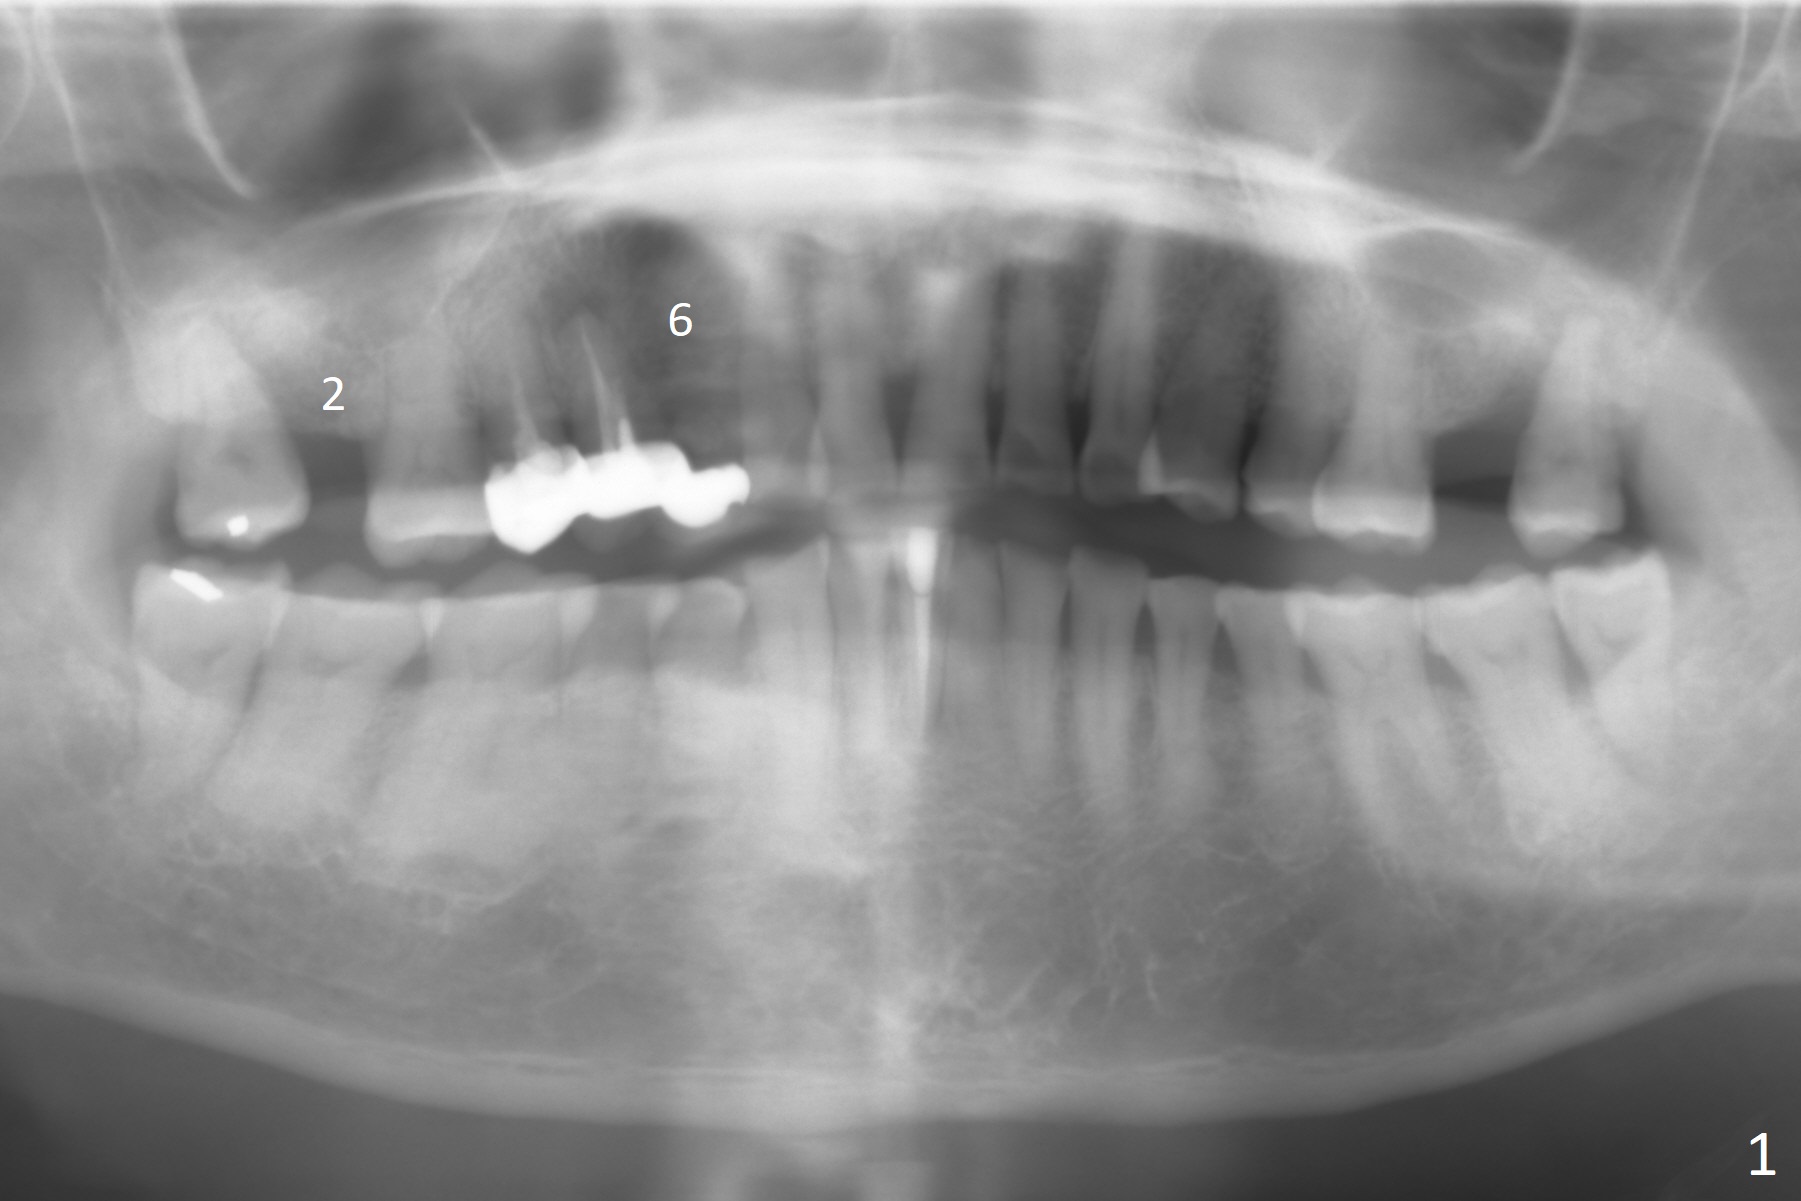

A 59-year-old woman has 2 issues: abscess mesiopalatal to #1 and a 30-year-old #4-6 cantilever FPD with a diastema between #6 and 7 (a cosmetic issue in the patient's mind, Fig.1). Since there is a lot of bone at #6 with apparently low bone density (Fig.2), a long implant will be placed: either 1- (SM, IS, or Tatum) or 2-pieces (UF). Take photos to show a gap mesioapical to the pontic and the narrow ridge (incisal view) after pontic removal. Use Magic Split for access and initial bone expansion.